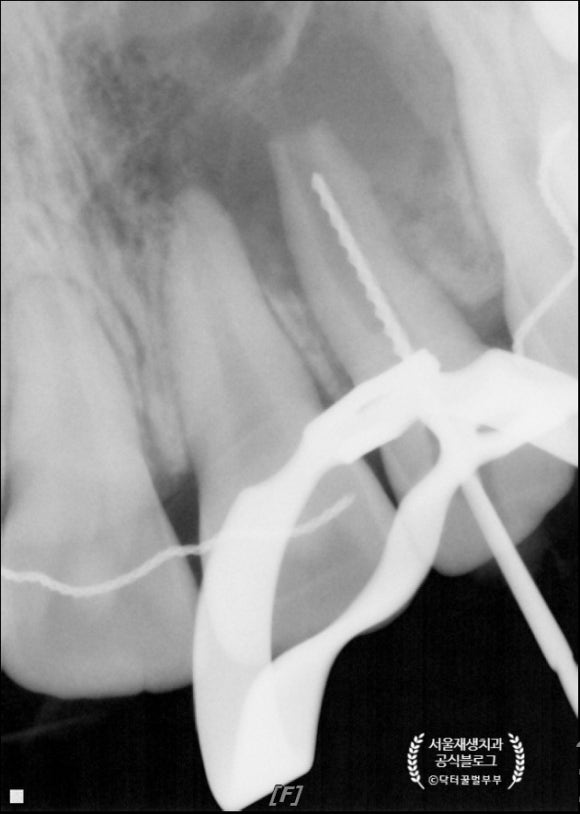

근관 치료용 파일로 뿌리의 길이를 가늠해봅니다.

뿌리 안팎으로 살아있는 줄기세포들이 있을 수 있기에 조심스럽게 살살 소독을 해줍니다.

첫 날은 소독제를 도포한 후 귀가!